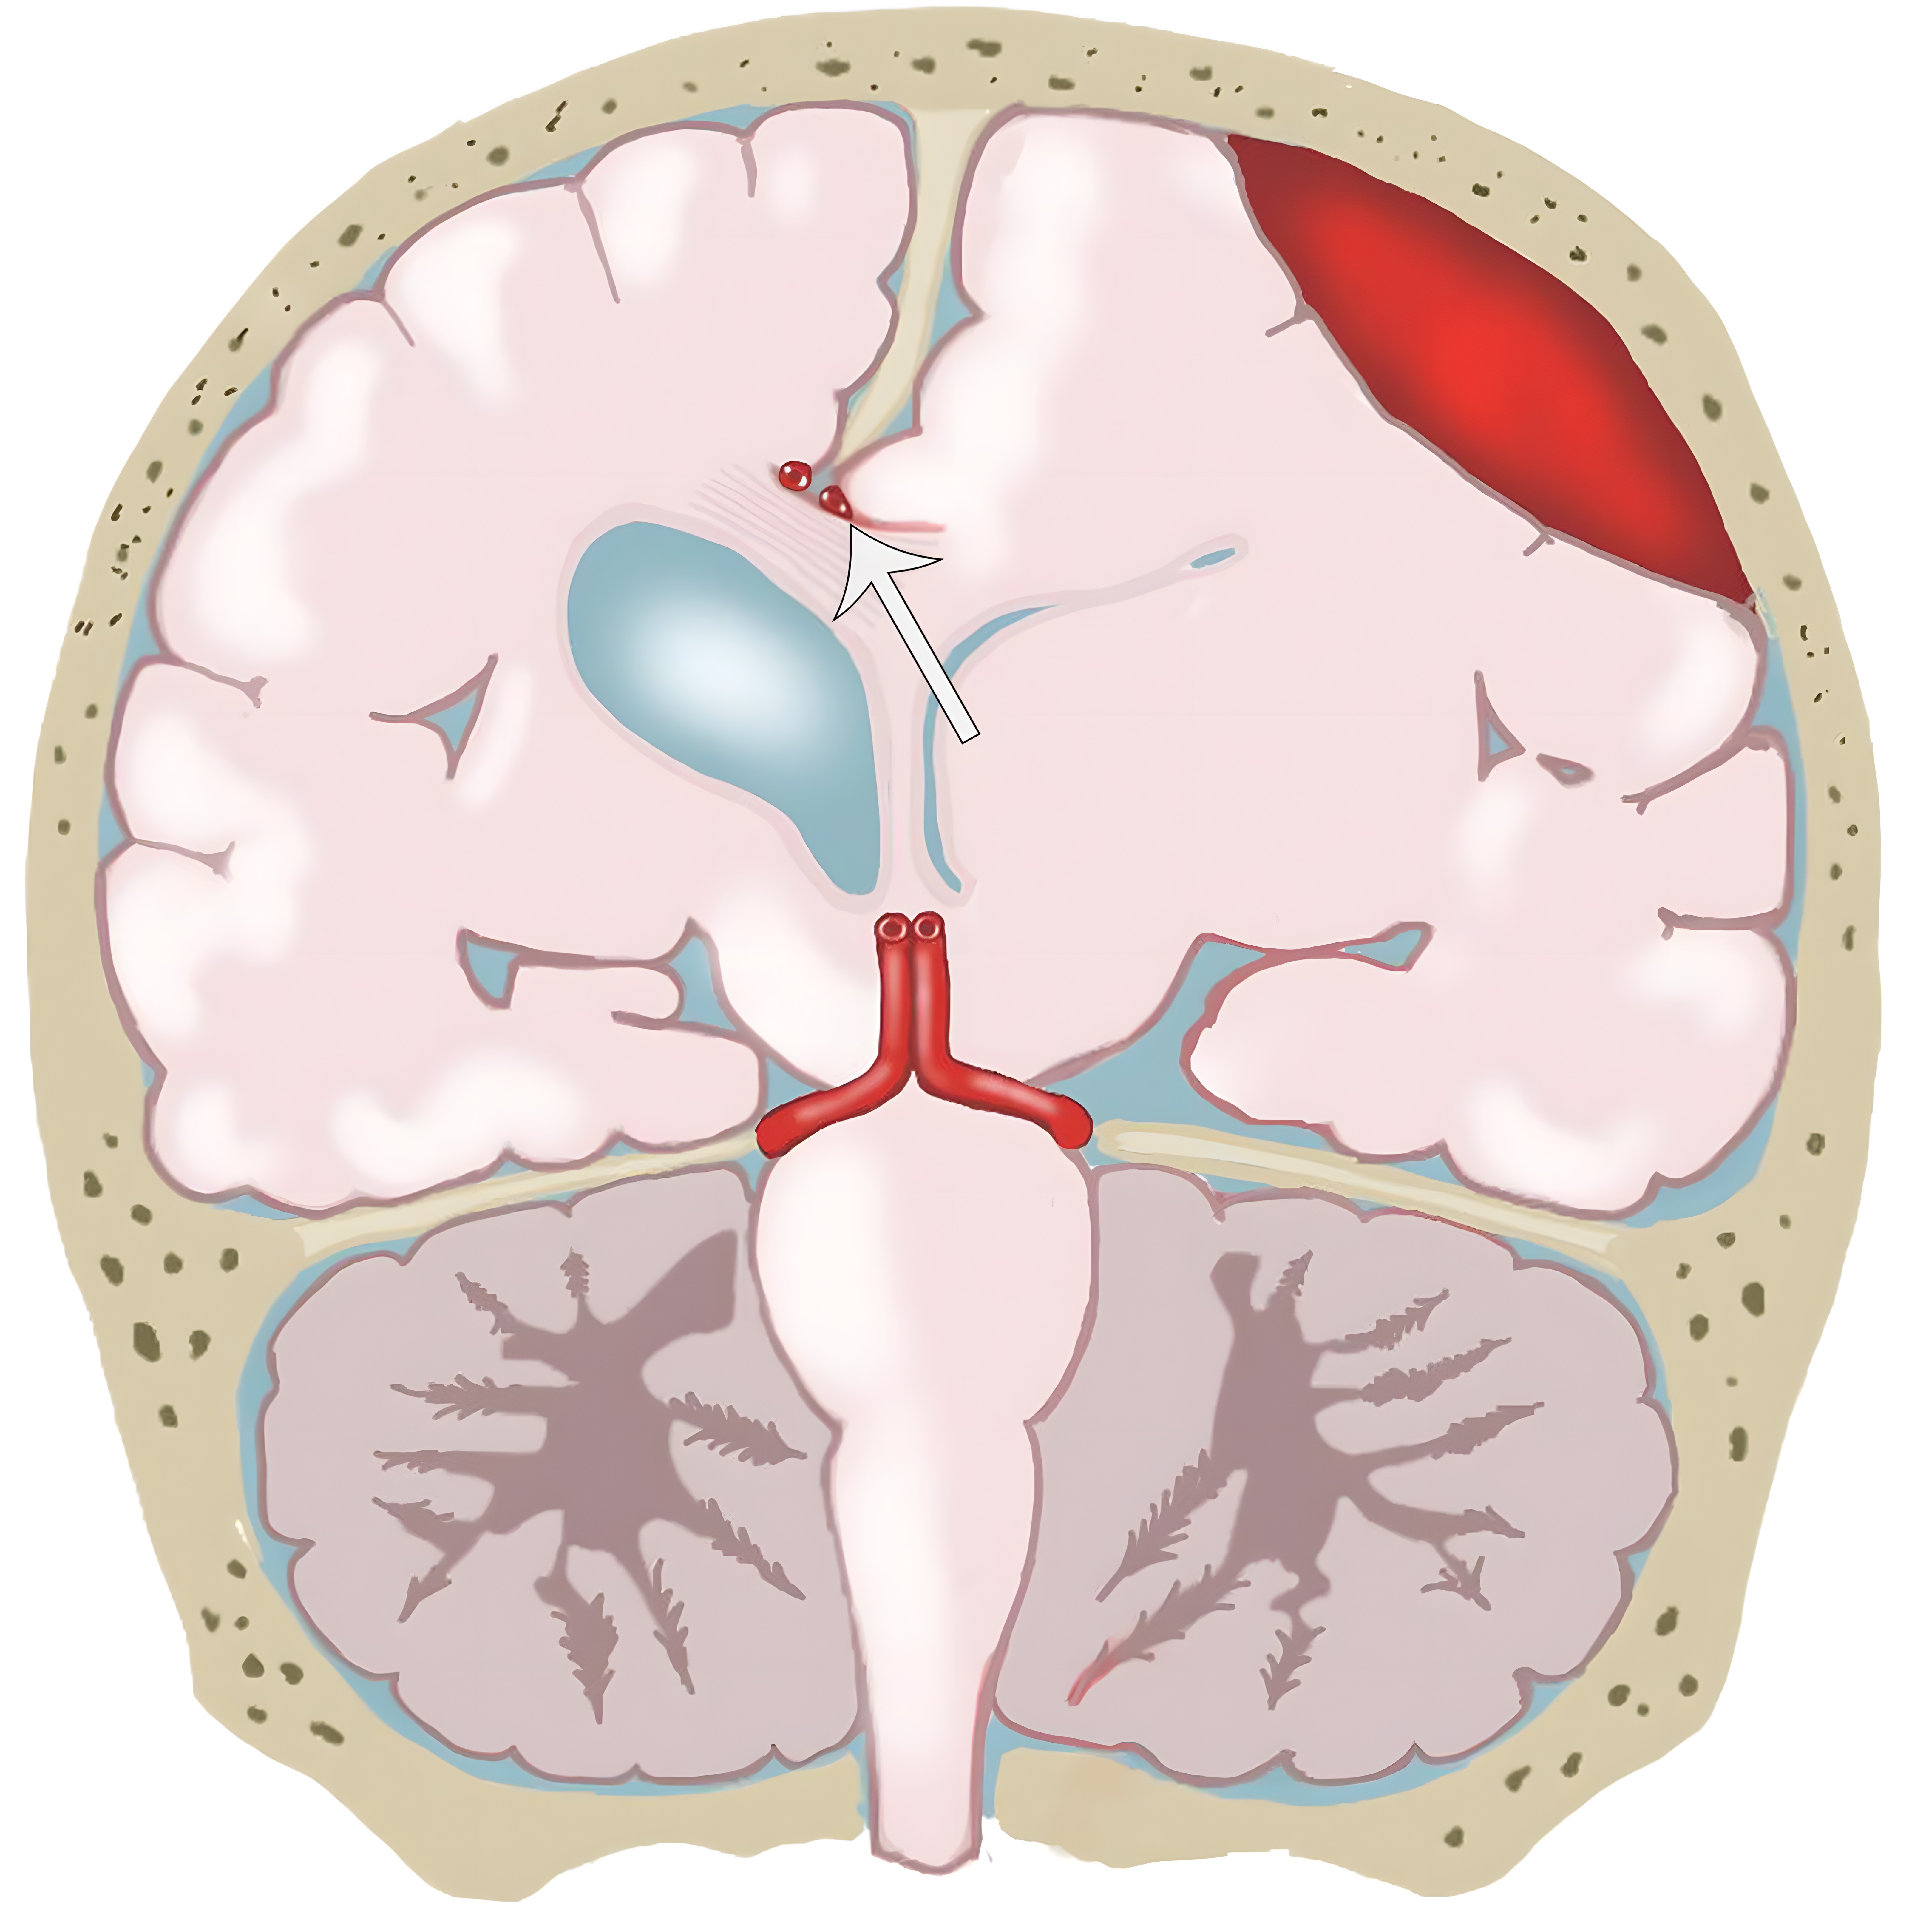

大脑镰下疝。平扫轴位CT示:右侧硬膜下血肿(*)伴混合密度影,表明处于不同时期的血液,血肿推挤使透明隔相对于中线(白色虚线)向左侧移位(白色长箭头)。右侧侧脑室受压,但是左侧侧脑室扩张。

e10b81f69aecfde7ed5f5612478dbcdc.jpeg

33岁男性,生殖细胞肿瘤脑转移患者的大脑镰下疝:冠状增强CT示大脑穹隆游离缘下方的扣带回从左向右疝入(白色弯箭头),并伴同侧胼胝体(*)的下侧移位,注意同侧脑室受压和对侧脑室的扩张(白色箭头)。

b970e936c5e18c5c1ffcf84ad6aaa810.jpeg

分房性硬膜下血肿及大脑镰下疝。左侧额叶挤压大脑镰(白色短箭头),以及蛛网膜下腔的消失。同时需要注意室间孔略向右侧移位(白色长箭头)。